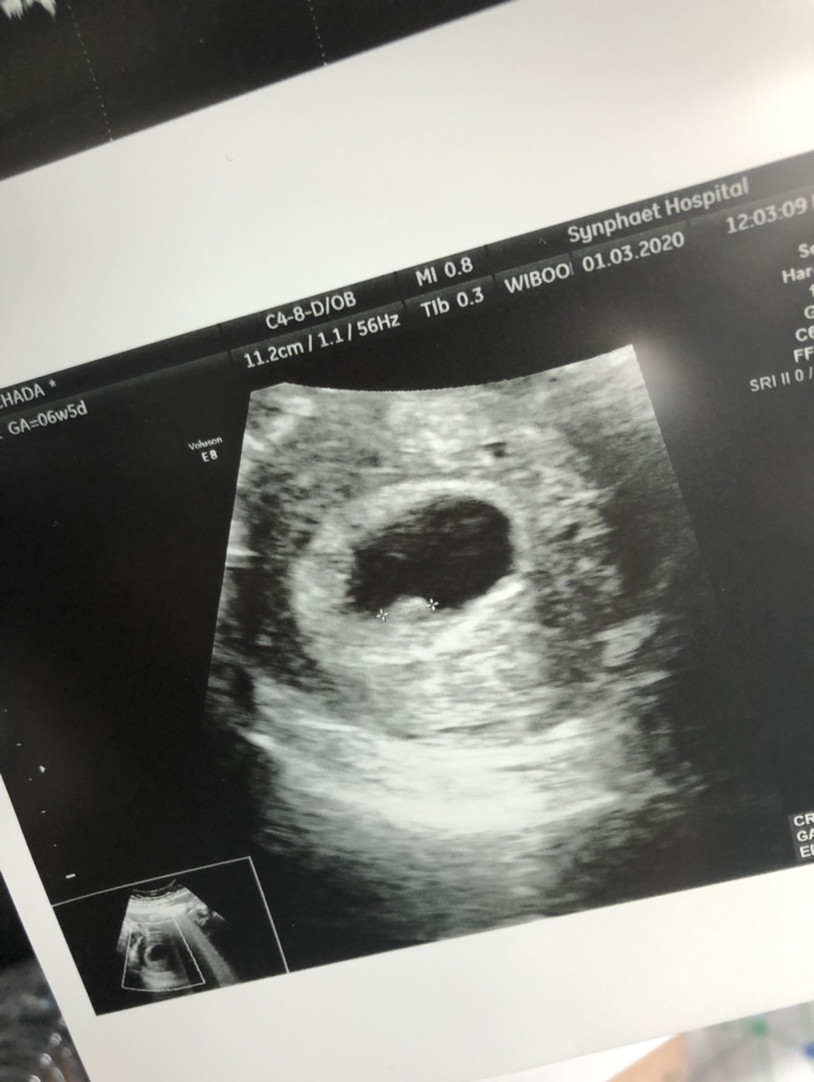

ตอน 6w 3d